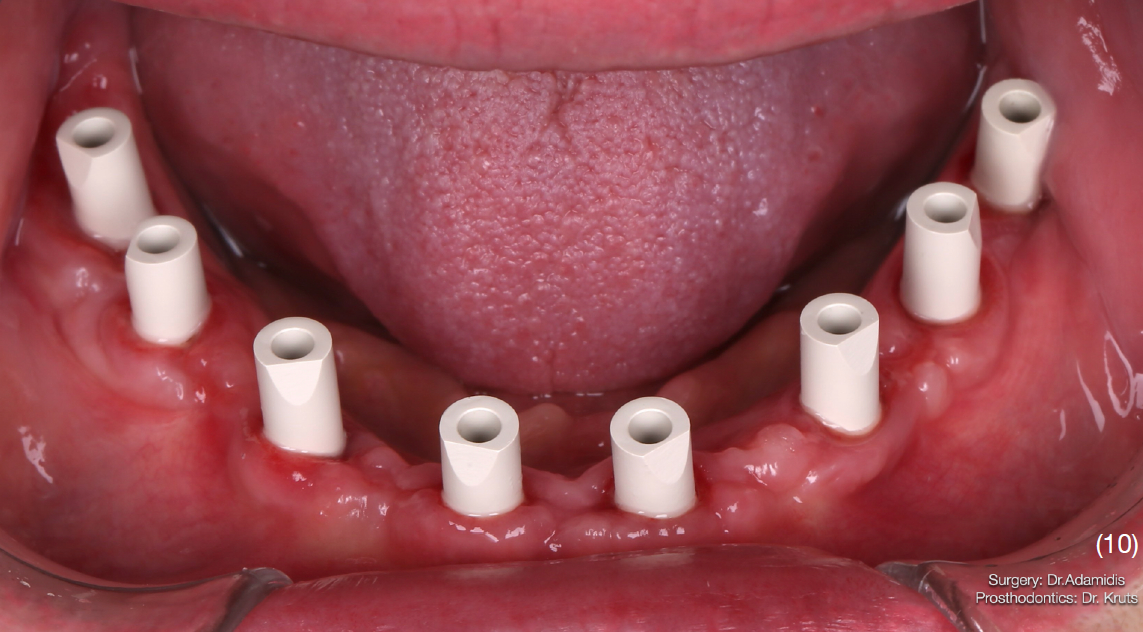

Етап протезування

Через 4 місяці після імплантації на нижній щелепі пацієнт був викликаний для заміни провізорної реставрації на постійну. Було відмічено дефіцит кератинізовних прикріплених ясен в 4 квадранті, що могло поставити під ризик стабільність імплантатів та естетичні параметри.

Тому було проведено м'якотканинну аугментацію технікою Strip в даній ділянці.

Протезування проводилось з використанням цифрового протоколу.

На нижню щелепу було виготовлено роздільну конструкцію. В бічних ділянках – мостоподібні протези на гвинтовій фіксації з рівня імплантату.

У фронтальній ділянці комбінована конструкція – каркас із діоксиду цирконію, фіксований до імплантатів гвинтами, на який цементуються коронки із прес-кераміки. Такий тип конструкції вибрано через високу надійність та прогнозованість в довготривалій перспективі, що підтверджується даними клінічних досліджень, а також легкість в обслуговуванні.

Верхню щелепу реабілітовано коронками з опорою на зуби та імплантати.